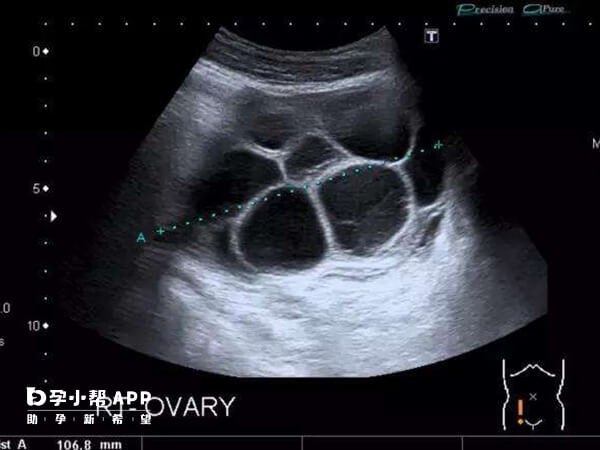

若是患者卵巢功能不好,那么在打夜针之后的第二天可能会引起卵巢过度刺激综合征,这可能导致孕酮升高,卵泡早排,从而出现排尿多的情况。